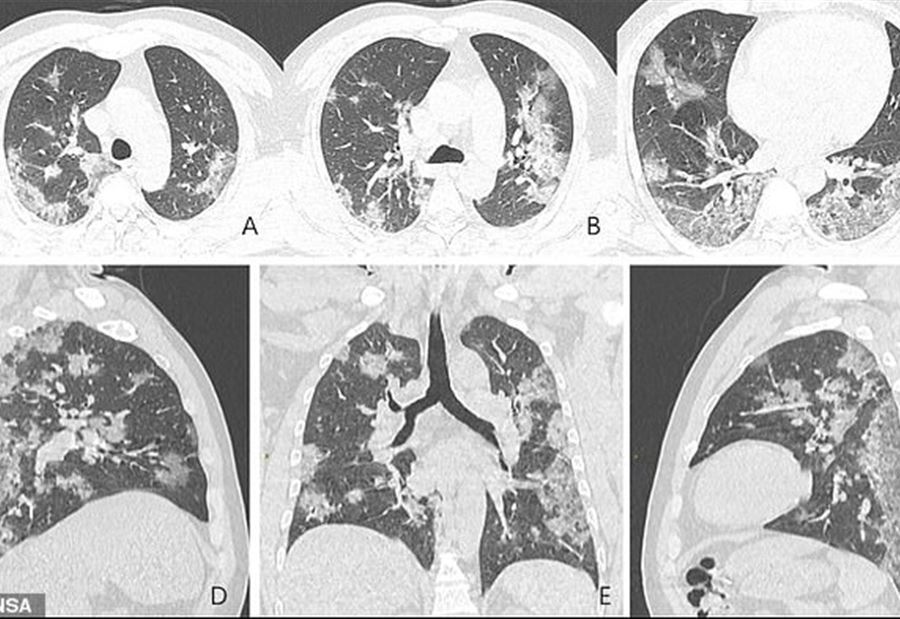

بالصور: "كورونا" في رئتي المُصاب

نشر موقع متخصص في التصوير بالأشعة المقطعية والسينية مجموعة من الصور قال إنها لرئتين مصابتين بفيروس كورونا المستجد.

علامات المرض التي بدت جلية في صور الأشعة، أظهرت تشابها كبيرا بين كوفيد-19 وفيروس السارس الذي أصاب الصين العام 2003.

وكشفت الأشعة السينية وجود بقع في الرئتين، وقال الموقع أن تلك البقع هي التي تفصح عن المرض لدى إجراء المريض الاختبار الأول أو عند اشتباه الأطباء في إصابته.

وذكر الموقع أن "التصوير المغناطيسي للجهاز التنفسي لامرأة تبلغ من العمر 54 سنة أظهر أن لون تلك البقع أبيض".

وأظهر تصوير مغناطيسي آخر أجري على صدر مريض صيني يبلغ من العمر 44 عاما، ذات البقع البيضاء، وهو ما جعل الأطباء يؤكدون أن تلك البقع هي في الحقيقة "التجسيد الفعلي لكورونا داخل الرئتين".

الرجل، بحسب الموقع، كان يعمل في سوق الأسماك في "مركز الوباء" ووهان الصينية، وهناك أصيب بالعدوى.

المريض وضع شهر كانون الأول الماضي تحت الحجر الصحي، بعد أن كان يشتكي من قشعريرة كبيرة مصحوبة بسعال حاد وجاف، ليجرى بعدها تشخيص إصابته بالالتهاب الرئوي الحاد، وتوفي بعد ذلك بأسبوع.

بعد وفاته، أجري له تصوير للرئتين وظهرت مرة ثانية نفس البقع البيضاء.

وذات البقع البيضاء ظهرت كذلك، يضيف الموقع، على رئتي امرأة صينية من مقاطعة سيتشوان، تبلغ من العمر 45 عاما توفيت بعد إصابتها بالفيروس عند بداية انتشاره الكبير مطلع يناير.

يذكر أن دراسة حديثة أكدت أنّ "الأشعة المقطعية للصدر أفضل من الاختبارات المخبرية في تشخيص كورونا في مرحلة مبكرة".

وهو ما جعل الأطباء يؤكدون أن الأشعة المقطعية يجب أن تكون طريقة الفحص الأولية لدى الاشتباه في كورونا لتسريع عمليات التشخيص المبكرة.